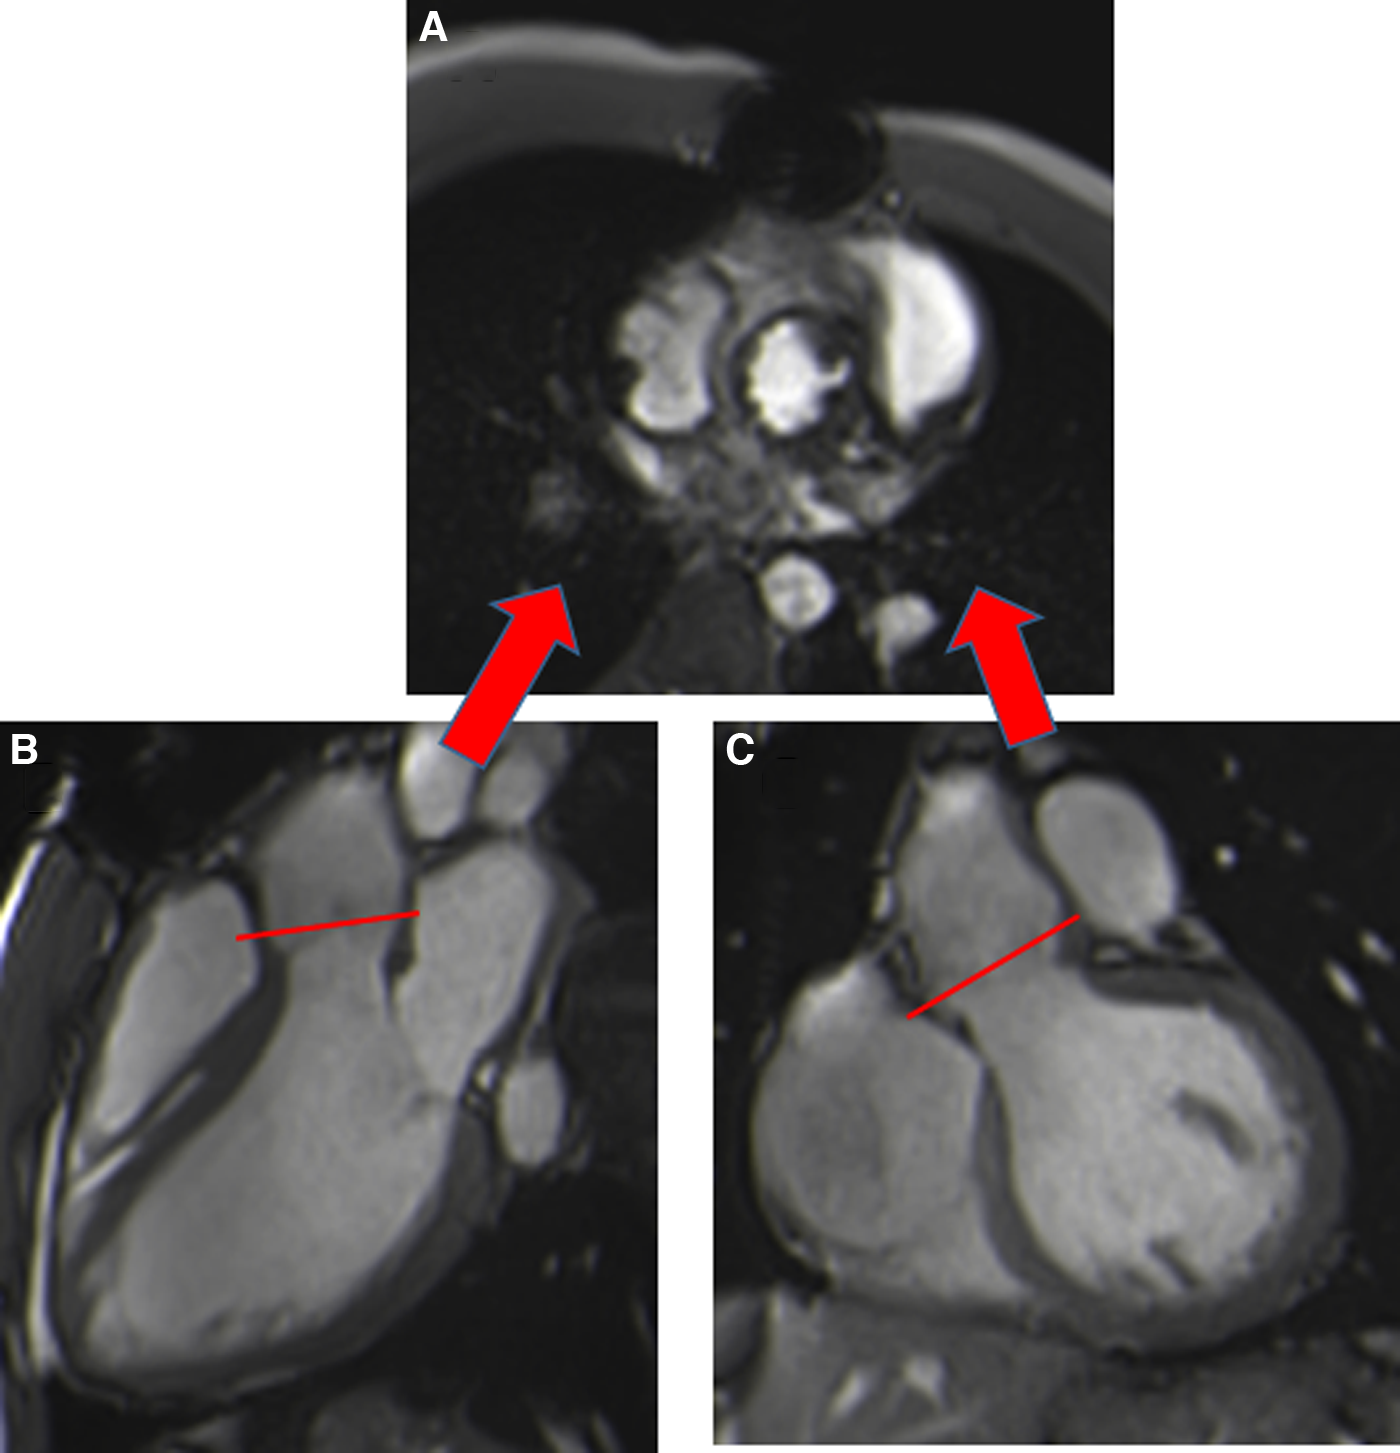

Figure 4

Visualization of the prosthetic orifice of a surgical stented bioprosthetic aortic valve (saint-jude 25) obtained from a three-chamber view (A). The visualization of leaflets for planimetry is more challenging (B).

In the absence of specific CMR reference values, those obtained by echocardiography are used (16). A close agreement between CMR and transthoracic and transoesophageal echocardiography has been shown for surgical stented and stentless prostheses with a normal orifice area, with feasibility for 95.4% of patients but reduced image quality due to artifacts for 15.4% (17).

Susceptibility to artefacts can be extensive for patients with TAVI, despite the absence of sternal wire artefacts, especially for the Corevalve® prosthesis due to a large stent from the LVOT beyond the sinotubular junction, making measurement of the orifice area unfeasible. Aortic orifice planimetry can also be challenging for the Edwards-Sapien® prosthesis (Figure 5).